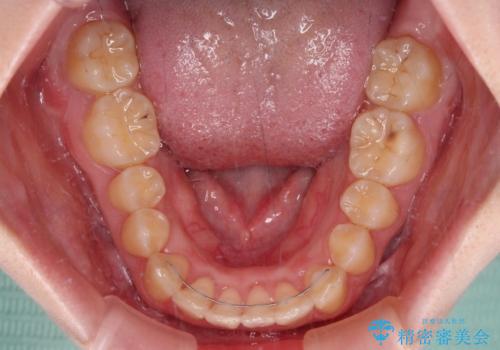

カリエールディスタライザーやワイヤー矯正を併用したことで、確実かつ短期間で治療を終えることができました。